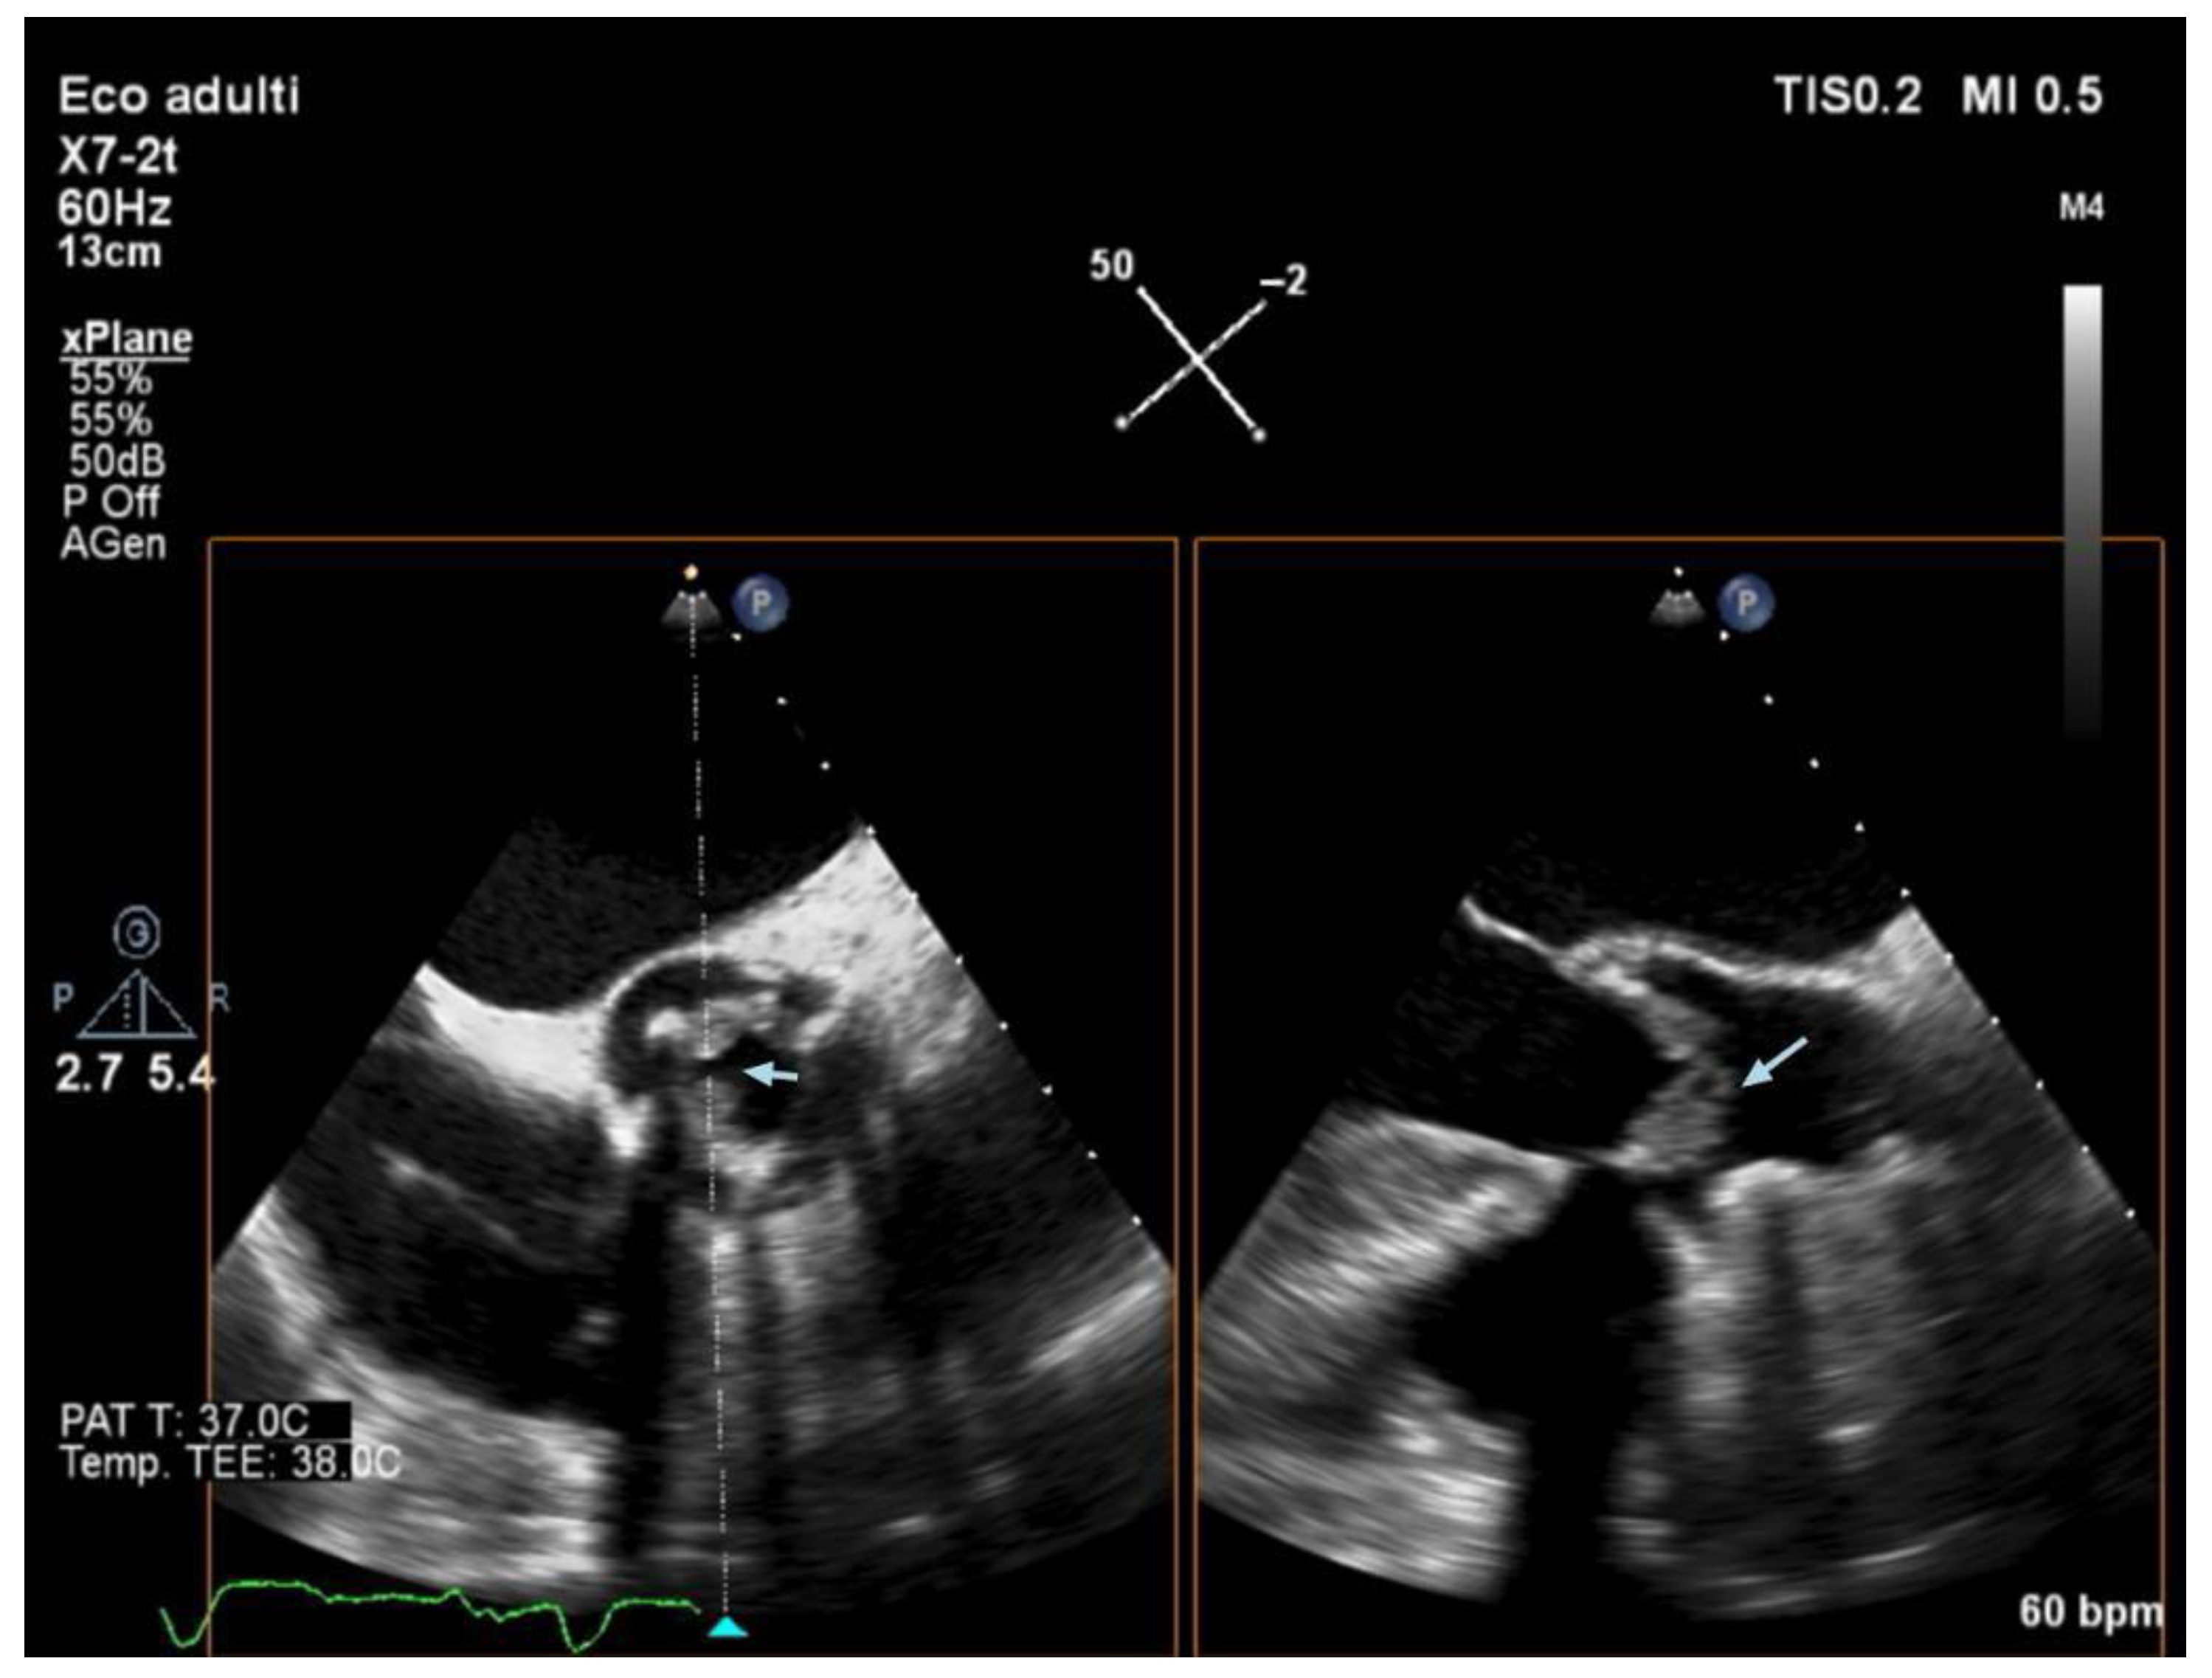

3.5. Echocardiography and Localization of IE